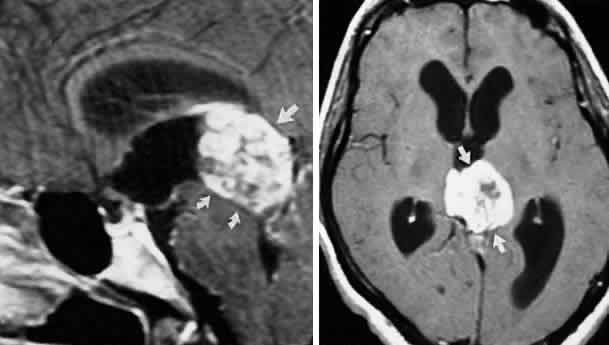

INTERPEDUNCULAR LESIONS

Basal lesions, including the rare rostral basilar artery aneurysm, may encroach on the oculomotor nerves as they exit in the interpeduncular space. Such slow-growing aneurysms, either saccular or fusiform, may present as partial oculomotor palsies with or without involvement of pyramidal tracts, and without subarachnoid hemorrhage.87 Aneurysms of the posterior communicating artery, on the other hand, are probably the most common lesions causing acute spontaneous oculomotor palsies (Fig. 12). According to Hyland and Barnett,88 the oculomotor palsy that occurs with posterior communicating aneurysm is not necessarily due to mass effect per se, but rather is attributed to hemorrhage that suddenly enlarges the aneurysmal sac to which the oculomotor nerve is adherent, or to hemorrhage into the substance of the nerve itself. Most patients present, therefore, with an intensely painful, complete unilateral oculomotor palsy in association with other signs and symptoms of subarachnoid hemorrhage. Few patients with symptomatic posterior communicating aneurysms are found in office waiting rooms: they are usually obtunded or comatose in emergency rooms.

Fig. 12. Sudden total right ophthalmoplegia accompanied by orbital pain, due to posterior communicating artery aneurysm. A. Complete right ptosis. B. Right eye in abducted position, with dilated pupil, fixed to light. C. Failure of adduction on left gaze. D. Right eye intorts (arrow) on downward gaze, indicating retained function of fourth nerve. E. Contrast-enhanced T-1 weighted MRI axial section shows aneurysm (arrows). Confirmed by angiography.